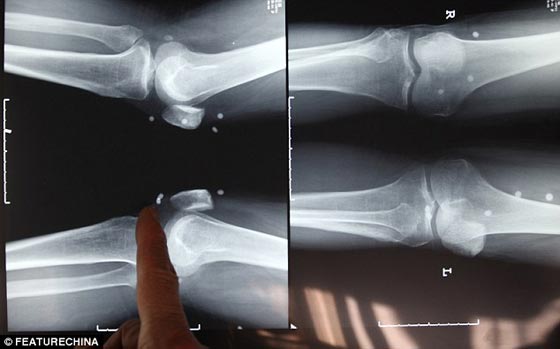

تم استخراج 42 لؤلؤة من جسد الصيني زو فنج بعد خضوعه لعملية جراحية. وكان قد تم زرع الـ 42 لؤلؤة من طبيب مزيف لعلاج آلام أصابت ظهره حين نصحه أحد جيرانه بزيارة طبيب بمقاطعة أخرى يدعي أنه يستخدم الطب الصيني القديم في علاج مثل تلك الحالات. وما إن عاد الرجل إلى مقاطعته، حتى بدأ يعاني من آلام مبرحة في مناطق متفرقة من جسده، وفي مفاصله بشكل خاص.

وبعد عامين من قيامه بزرع الـ 42 لؤلؤة، وجد نفسه غير قادر على تحمل الآلام، ما دفعه لزيارة مستشفى متخصص في علاج آلام المفاصل بعد أن كان قد بحث عن الطبيب الآخر إنما لم يجده. وقد أكد الجراح الذي أجرى العملية أن الـ 42 لؤلؤة تسببت في تلف حاد بالهيكل العظمي، ولا سيما مفصل الورك الذي أصبح يتطلب عملية جراحية أخرى لاستبداله، حسبما جاء في صحيفة "دايلي ميل" البريطانية.